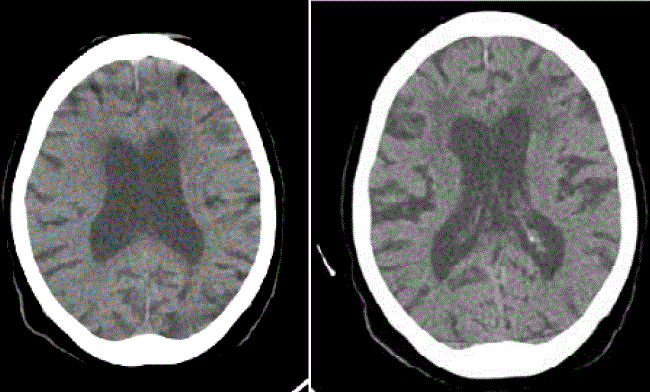

En la tomografía computadorizada (TC) de cerebro, se observó hidrocefalia con ventriculomegalia e hipodensidades periventriculares (figura 1) y en la de tórax de alta resolución, un patrón en vidrio esmerilado con atelectasia del lóbulo inferior pulmonar izquierdo (figura 2).